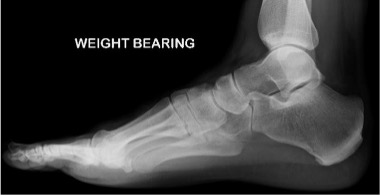

Lateral view foot (weightbearing)

Radiographic technique

Lateral X-ray beam centred on the base of the fifth metatarsal with the side of the foot against the image receptor.

Anatomical review areas

- Trochlear surface of the talus

- Facets of the subtalar joint and calcaneum

- Calcaneo-cuboid and talo-navicular (Chopart) joints

- Sustentaculum tali and sinus tarsi are usually apparent

- Midtarsal complex is partially obscured by superimposition of the cuneiforms and metatarso-cuneiform articulations, although the first metatarso-cuneiform joint is usually seen

- The lesser metatarsals are superimposed over each other, although the first metatarsal, hallux, and first metatarso-phalangeal joint should be distinguishable